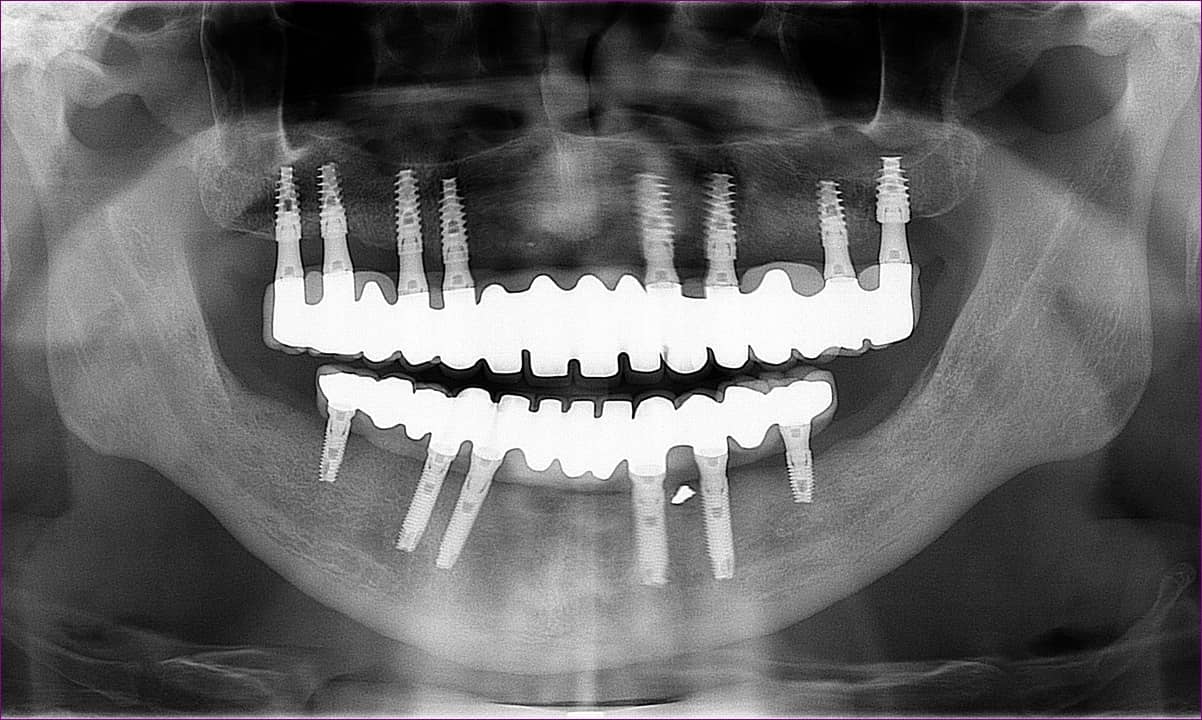

Az elkészült pótlás

A becsavarozott, átadott alsó-felső rögzített pótlás röntgenfelvétele az alább látható.

Páciensünk a kezelés során végig együttműködő és türelmes volt, a végeredménnyel pedig maximálisan elégedett volt.